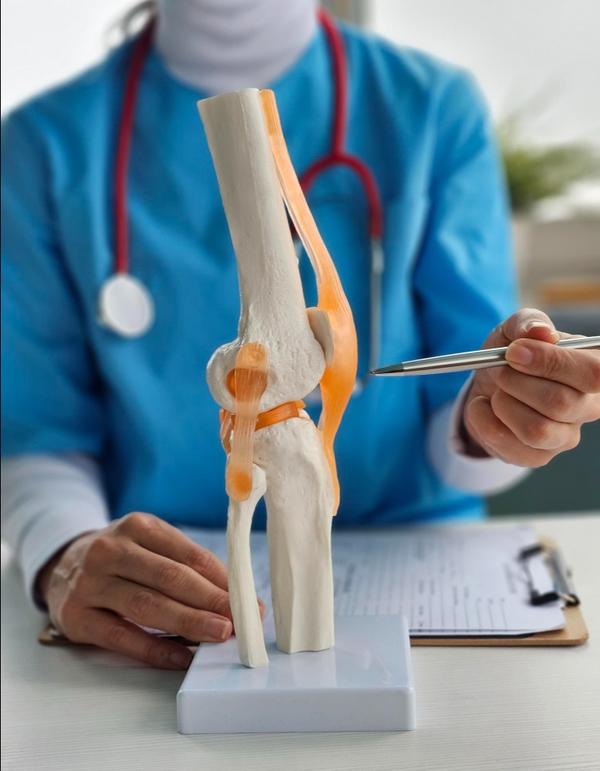

What We Cure

Shoulder Arthroplasty

Shoulder arthroplasty is a surgical procedure used to replace damaged or arthritic parts of the shoulder joint with artificial components. It is typically recommended for patients with severe osteoarthritis, complex fractures, or rotator cuff-related joint degeneration that limits mobility and causes chronic pain. At Rapha Sports and Regenerative Orthopaedics, our surgeons offer advanced shoulder replacement options tailored to each patient’s condition, lifestyle, and functional goals. Types of Shoulder Arthroplasty: Total Shoulder Replacement (Anatomic): Replaces both the ball (humeral head) and socket (glenoid) with prosthetic components. Best suited for patients with intact rotator cuff muscles and primary osteoarthritis. Reverse Shoulder Replacement: Reverses the normal anatomy of the shoulder by placing the ball component on the shoulder blade and the socket on the upper arm. Ideal for patients with rotator cuff tears, cuff tear arthropathy, or complex fractures. Hemiarthroplasty: Replaces only the ball portion of the joint. Often used in certain fractures or where the socket remains healthy. Partial/Stemless Shoulder Replacement: A bone-preserving option for select patients with less extensive damage, offering quicker recovery and less invasive techniques. Our multidisciplinary team ensures seamless care—from pre-operative planning to post-operative physiotherapy—focused on restoring function, reducing pain, and supporting long-term joint health.